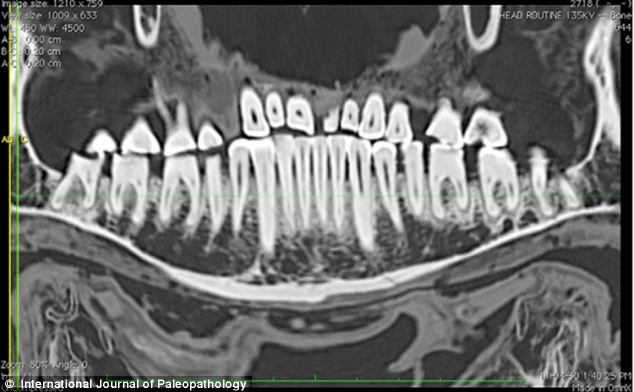

相比過去的研究器材,CT掃描儀使研究團(tuán)隊(duì)能夠更清晰詳盡地觀察填充物。

CT片顯示了木乃伊左邊第一顆門牙(左圖)和右邊第二顆門牙(右圖)的磨損狀況。